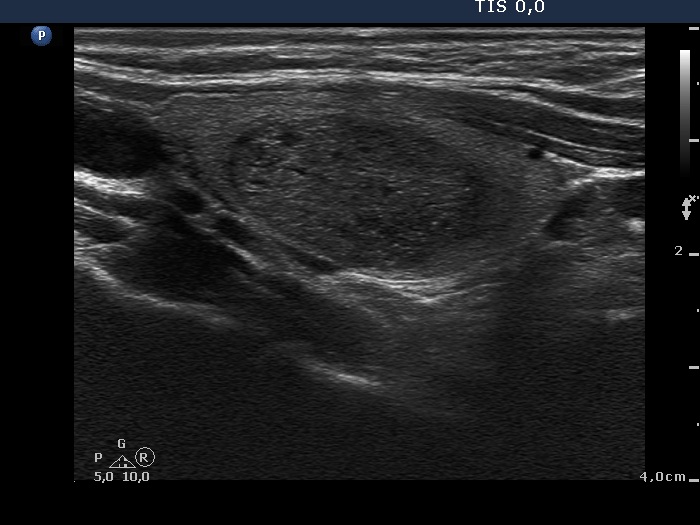

Ultrasonography. The thyroid was echonormal. There were multiple moderately lesions in the right lobe. The largest one had non-specific intranodular hyperechogenic granules, halo sign and both perinodular and intranodular blood flow.